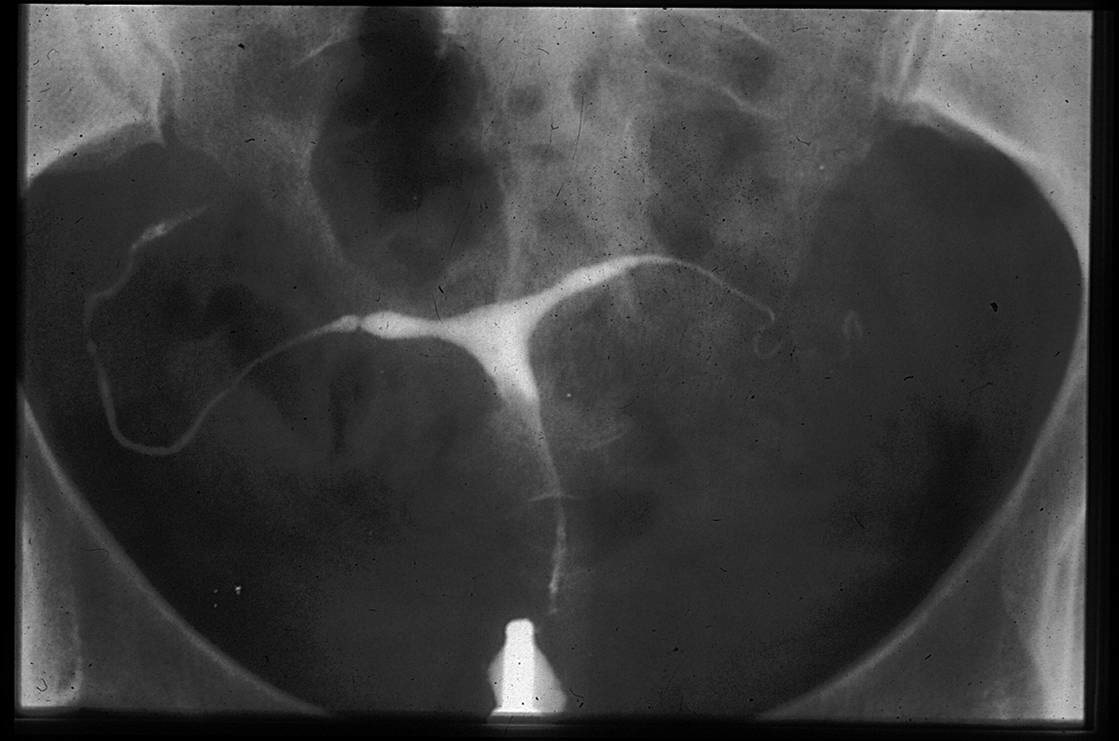

Utérus : utérus en « T », hypoplasique, avec rétrécissements.

En comparaison avec un utérus normal (fig 4), exemples de malformations typiques : utérus en T et hypoplasique (fig 5), utérus en T avec bords irréguliers et rétrécissements du corps (fig 6) et utérus en T avec rétrécissements au niveau du corps et des cornes (Fig 7).